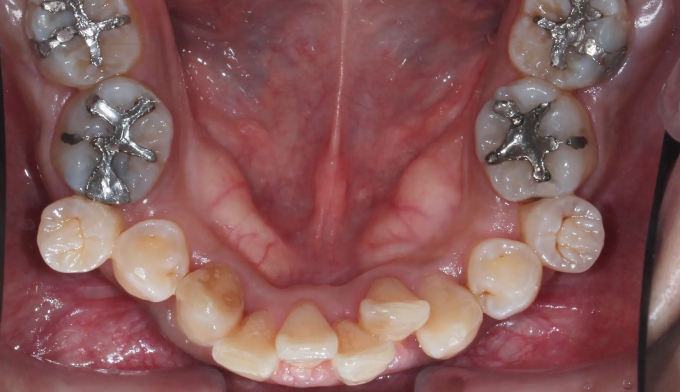

뻐드러진 앞니로 인한 돌출입과, 구강위생관리 부족으로 인한 다수의 충치가 관찰된 케이스입니다.

교정시작 전 충치가 많은 분들은 교정치료과정에서 더 많은 충치가 생길 가능성이 매우 높기 때문에 먼저 양치질교육을 비롯한 전반적인 구강위생교육이 이루어져야 합니다. 그리고 급한 충치를 먼저 치료하고 교정치료에 들어갑니다.

충치가 진행된 부분이 워낙 광범위하고 많아, 무리해서 치아를 전부 치료하지 않았습니다. 최소한으로 치료하고 지켜보기로 하였습니다.